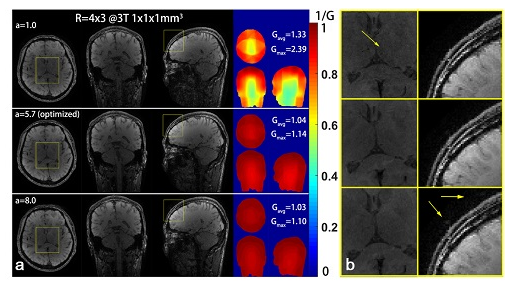

6.利用生物成像平台的联影磁共振成像系统,基于国际前沿的波浪鸡尾酒(Wave-CAIPI)快速三维成像技术,在国际上率先提出了一套快速有效的波浪(Wave)梯度参数优化方案;针对波浪梯度所存在的梯度零阶矩不为“零”这一关键问题,在国际上首次提出了一种新的截断式波浪梯度,不仅完善了磁共振快速三维成像理论基础,同时进一步推动了相关的高级磁共振快速三维成像技术走向临床应用

论文发表相关信息:

Parameter optimization framework on wave gradients of Wave-CAIPI imaging,Magnetic Resonance in Medicine,2020,Volume83,Issue5,Page1659-1672

关键技术支撑:磁共振成像技术